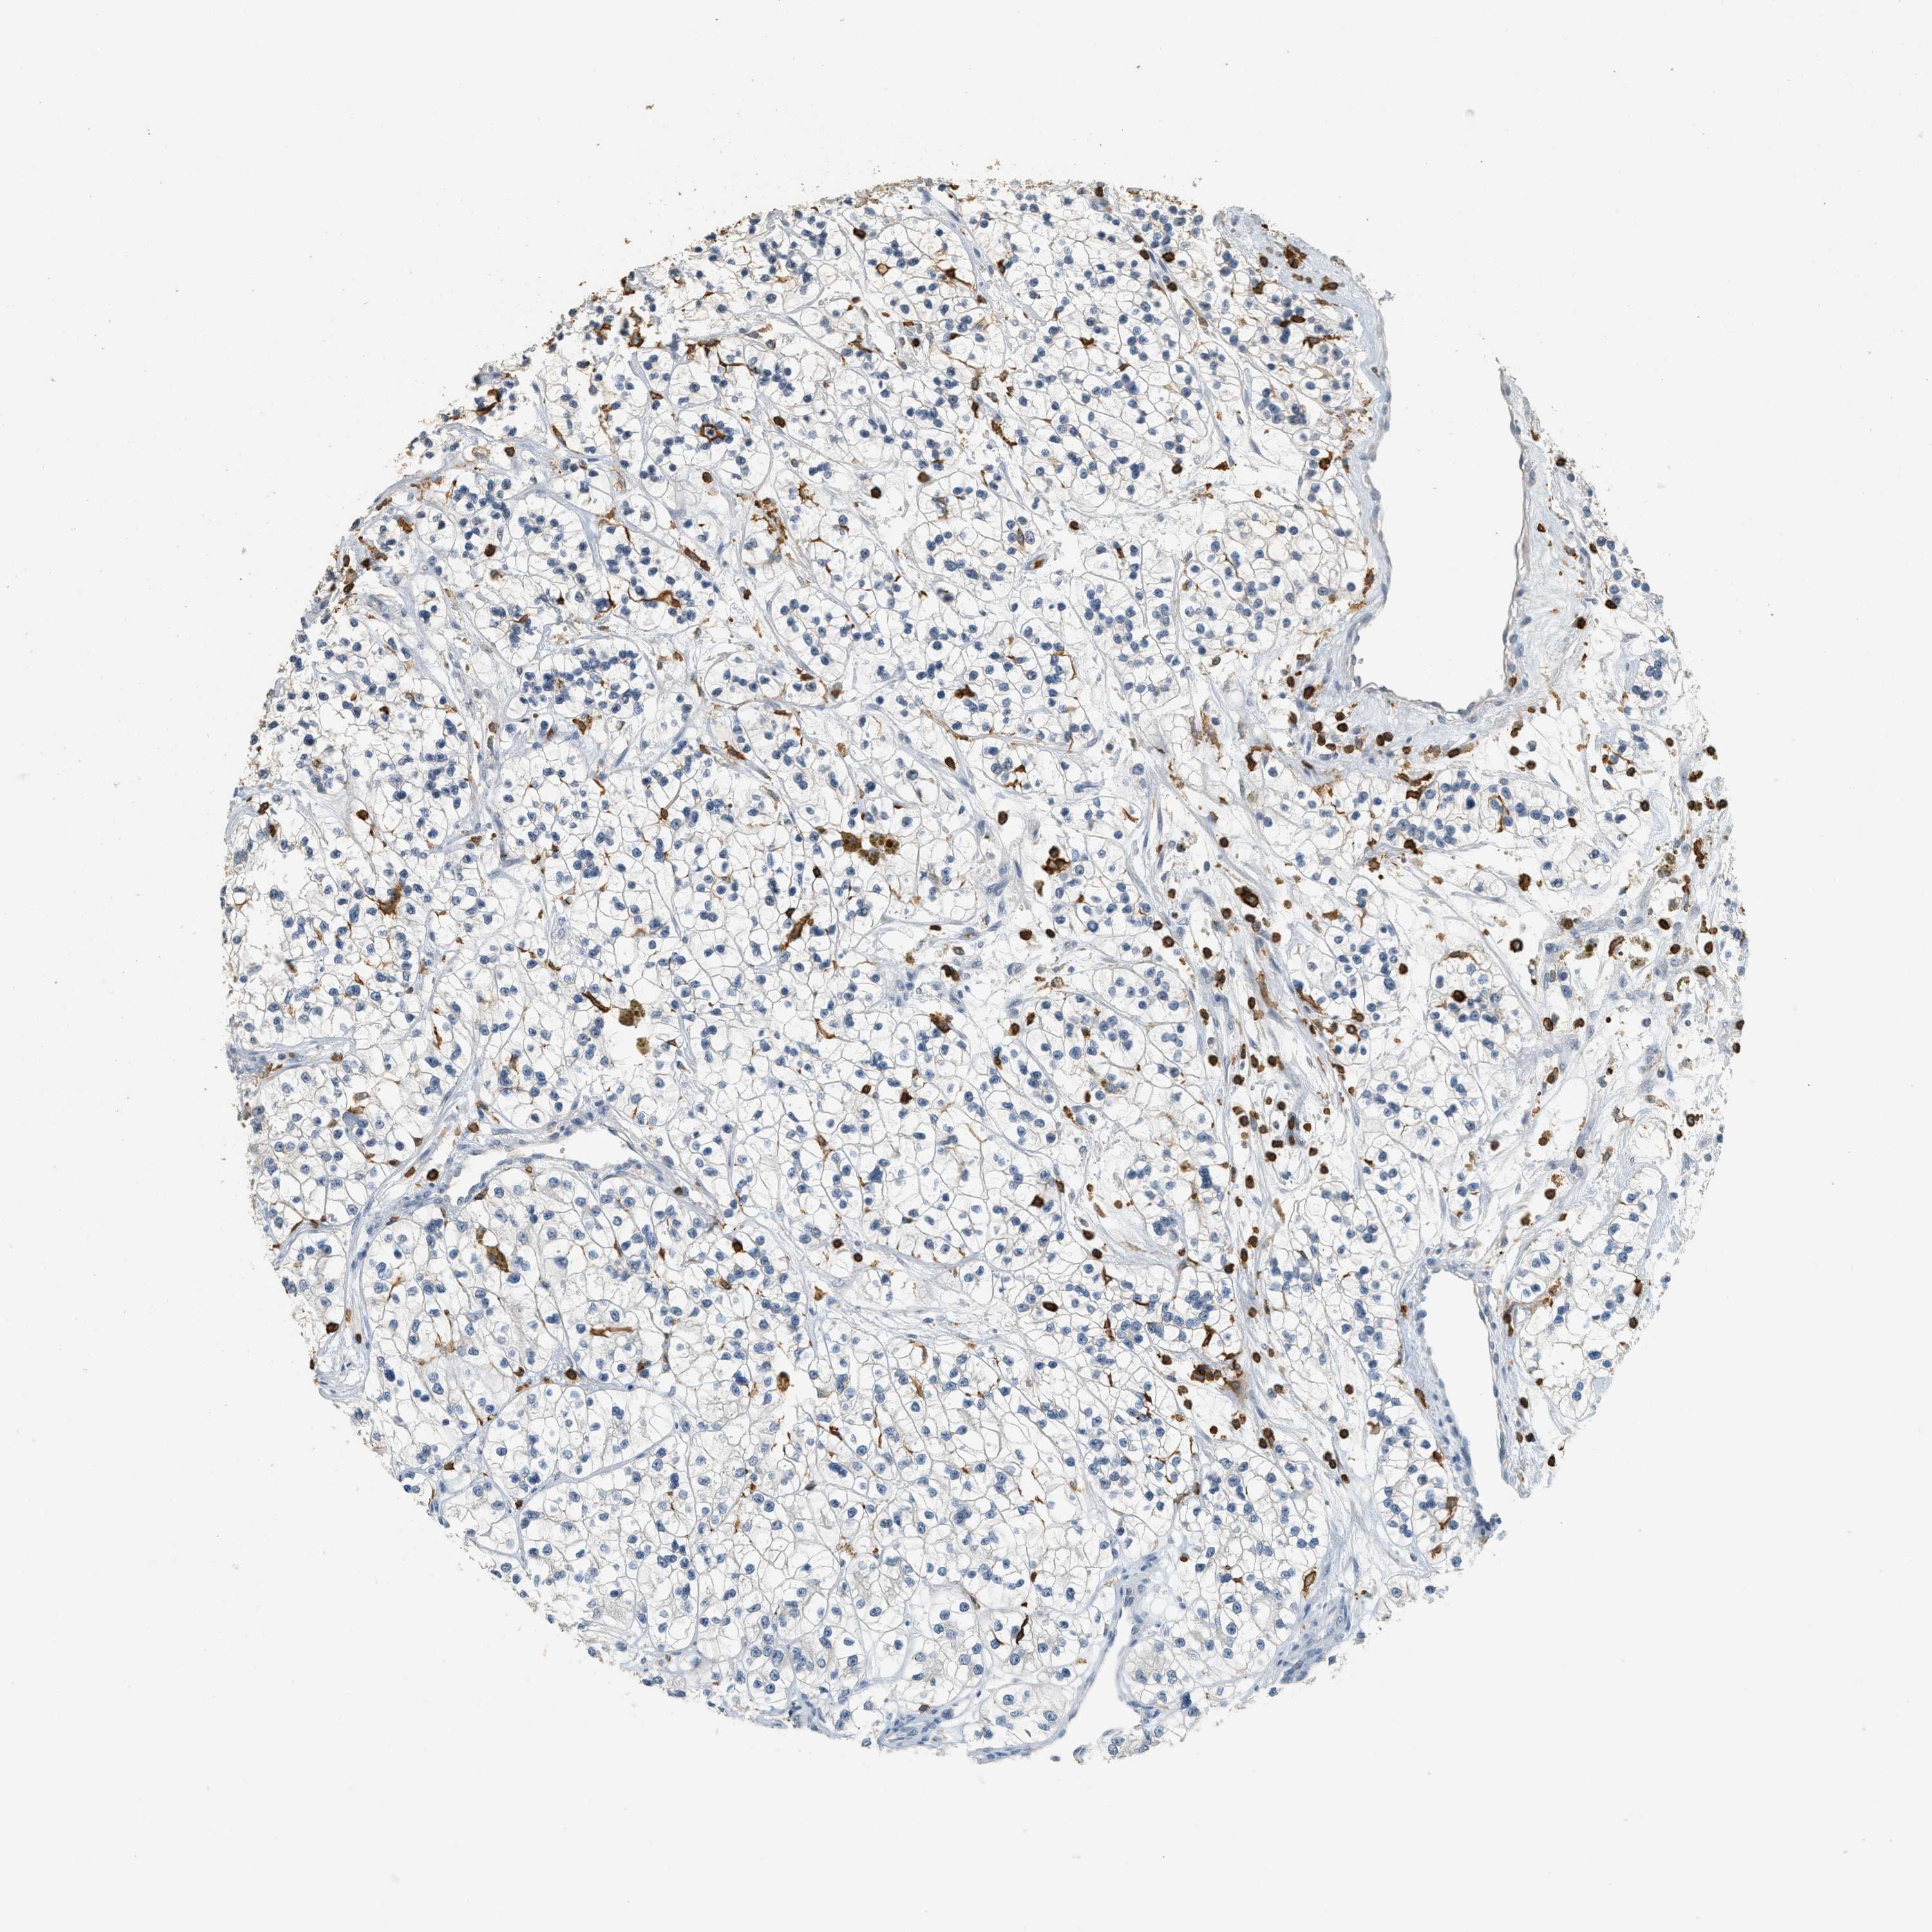

KIDNEY RENAL CLEAR CELL CARCINOMA (VALIDATION) - Interactive survival scatter ploti

The Survival Scatter plot shows the clinical status (i.e. dead or alive) for all individuals in the patient cohort, based on the same data that underlies the corresponding Kaplan-Meier plots. Patients that are alive at last time for follow-up are shown in blue and patients who have died during the study are shown in red.

The x-axis shows the expression levels (FPKM) of the investigated gene in the tumor tissue at the time of diagnosis. The y-axis shows the follow-up time after diagnosis (years). Both axes are complimented with kernel density curves demonstrating the data density over the axes. The top density plot shows the expression levels (FPKM) distribution among dead (red) and alive patients (blue). The right density plot shows the data density of the survived years of dead patients with high and low expression levels respectively, stratified using the cutoff indicated by the vertical dashed line through the Survival Scatter plot. This cutoff is automatically defined based on the FPKM cutoff that minimizes the p-score. The cutoff can be changed by dragging the vertical line or by entering a cutoff value in the square labeled "Current cut-off".

Under the Survival Scatter plot the p-score landscape (black curve; left axis) is shown together with dead median separation (red curve; right axis). Dead median separation is the difference in median mRNA expression between patients who have died with high and low expression, respectively. It is calculated as follows: median FPKM expression of dead patients with high expression - median FPKM expression of dead patients with low expression. This is intended to aid the user in visually exploring custom cutoffs and the associated p-scores and dead median separation.

Individual patient data is displayed and can be filtered by clicking on one or more of the category buttons on the top of the page. Categories describing expression level and patient information include: high, low, alive, dead, female, male and tumor stages. The scale of the x-axis can be toggled between linear and log-scale by clicking on the "x log" button. Mouse-over function shows TCGA ID, patient information and mRNA expression (FPKM) for each patient.

& Survival analysisi

Kaplan-Meier plots summarize results from analysis of correlation between mRNA expression level and patient survival. Patients were divided based on level of expression into one of the two groups "low" (under cut off) or "high" (over cut off). X-axis shows time for survival (years) and y-axis shows the probability of survival, where 1.0 corresponds to 100 percent.

LSP1 is not prognostic in Kidney Renal Clear Cell Carcinoma (validation)

Best expression cut offi

Based on the FPKM value of each gene, patients were classified into two groups and association between prognosis (survival) and gene expression (FPKM) was examined. The best expression cut-off refers the FPKM value that yields maximal difference with regard to survival between the two groups at the lowest log-rank P-value. Best expression cut-off was selected based on survival analysis .

When clicking on this number, the vertical dashed line indicating cut-off, the interactive survival plot, and the Kaplan-Meier curve will be adjusted to show results based on the best expression cut-off.

: 23.25

TCGA RNA samplesi

RNA-seq data is reported as average FPKM (number Fragments Per Kilobase of exon per Million reads), generated by the The Cancer Genome Atlas (TCGA) .

Normal distribution across the dataset is visualized with box plots, shown as median and 25th and 75th percentiles. Points are displayed as outliers if they are above or below 1.5 times the interquartile range. FPKM values of the individual samples are presented next to the box plot.

Average pTPM 45.1

Number of samples 100